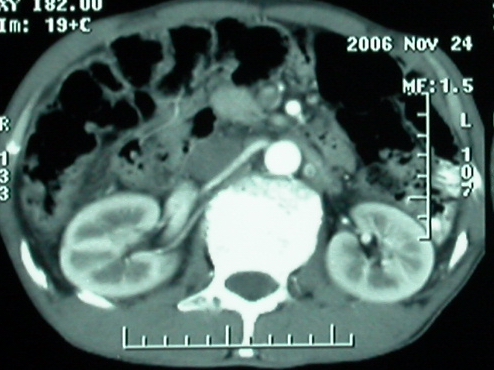

增强ct所见【动脉增强期】

门脉主干及肠系膜上静脉近端明显增粗,尤其前者呈等低混杂密度,增强后周围见轻度环形强化。明显占位效应。肝内外胆管见大量气体影。胆囊明显增大。

影像表现:胆囊扩张、肝内胆管不扩张,且见肝脏内树枝样气体影;十二指肠后方等密度占位,中心有不规则囊变区。增强实质部分轻度强化。下部腔静脉未强化------有栓子吗?

1、胰头部占位:胰管轻度扩张(可疑双管征),主要考虑恶性肿瘤,胰头癌?十二指肠间质瘤?后腹膜肿瘤?

2、门静脉高压症,主要考虑胰头部肿块压迫或者浸润所致肝前性门静脉主干受压;肝功能尚可,脾脏不大,无脾亢;

3、胆囊积液、肝胆管积气、胆道扩张伴有胆道感染;

4、右肝后上段占位(考虑肝胆管结石伴肝组织萎缩?)

5、下腔静脉受压;

6、左半肝缺失,原因不明?

7、有无门静脉癌栓?

8、有无淋巴结肿大?

ct表现:1,胰腺钩突后方肿块,不均强化,中心密度低,钩突及门静脉前移。2:肝右后叶不均强化灶,突出肝表面,3:胆囊明显增大,肝内胆管及肝总管内积气。4:腹腔内少量积液。